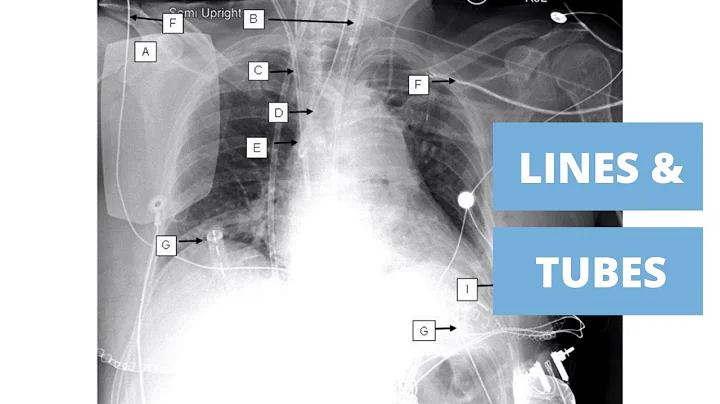

The ABCDE's to reading a chest xray! A: Airway. Look at the airway. It should be midline. Tumors, tension pneumothorax, large ...